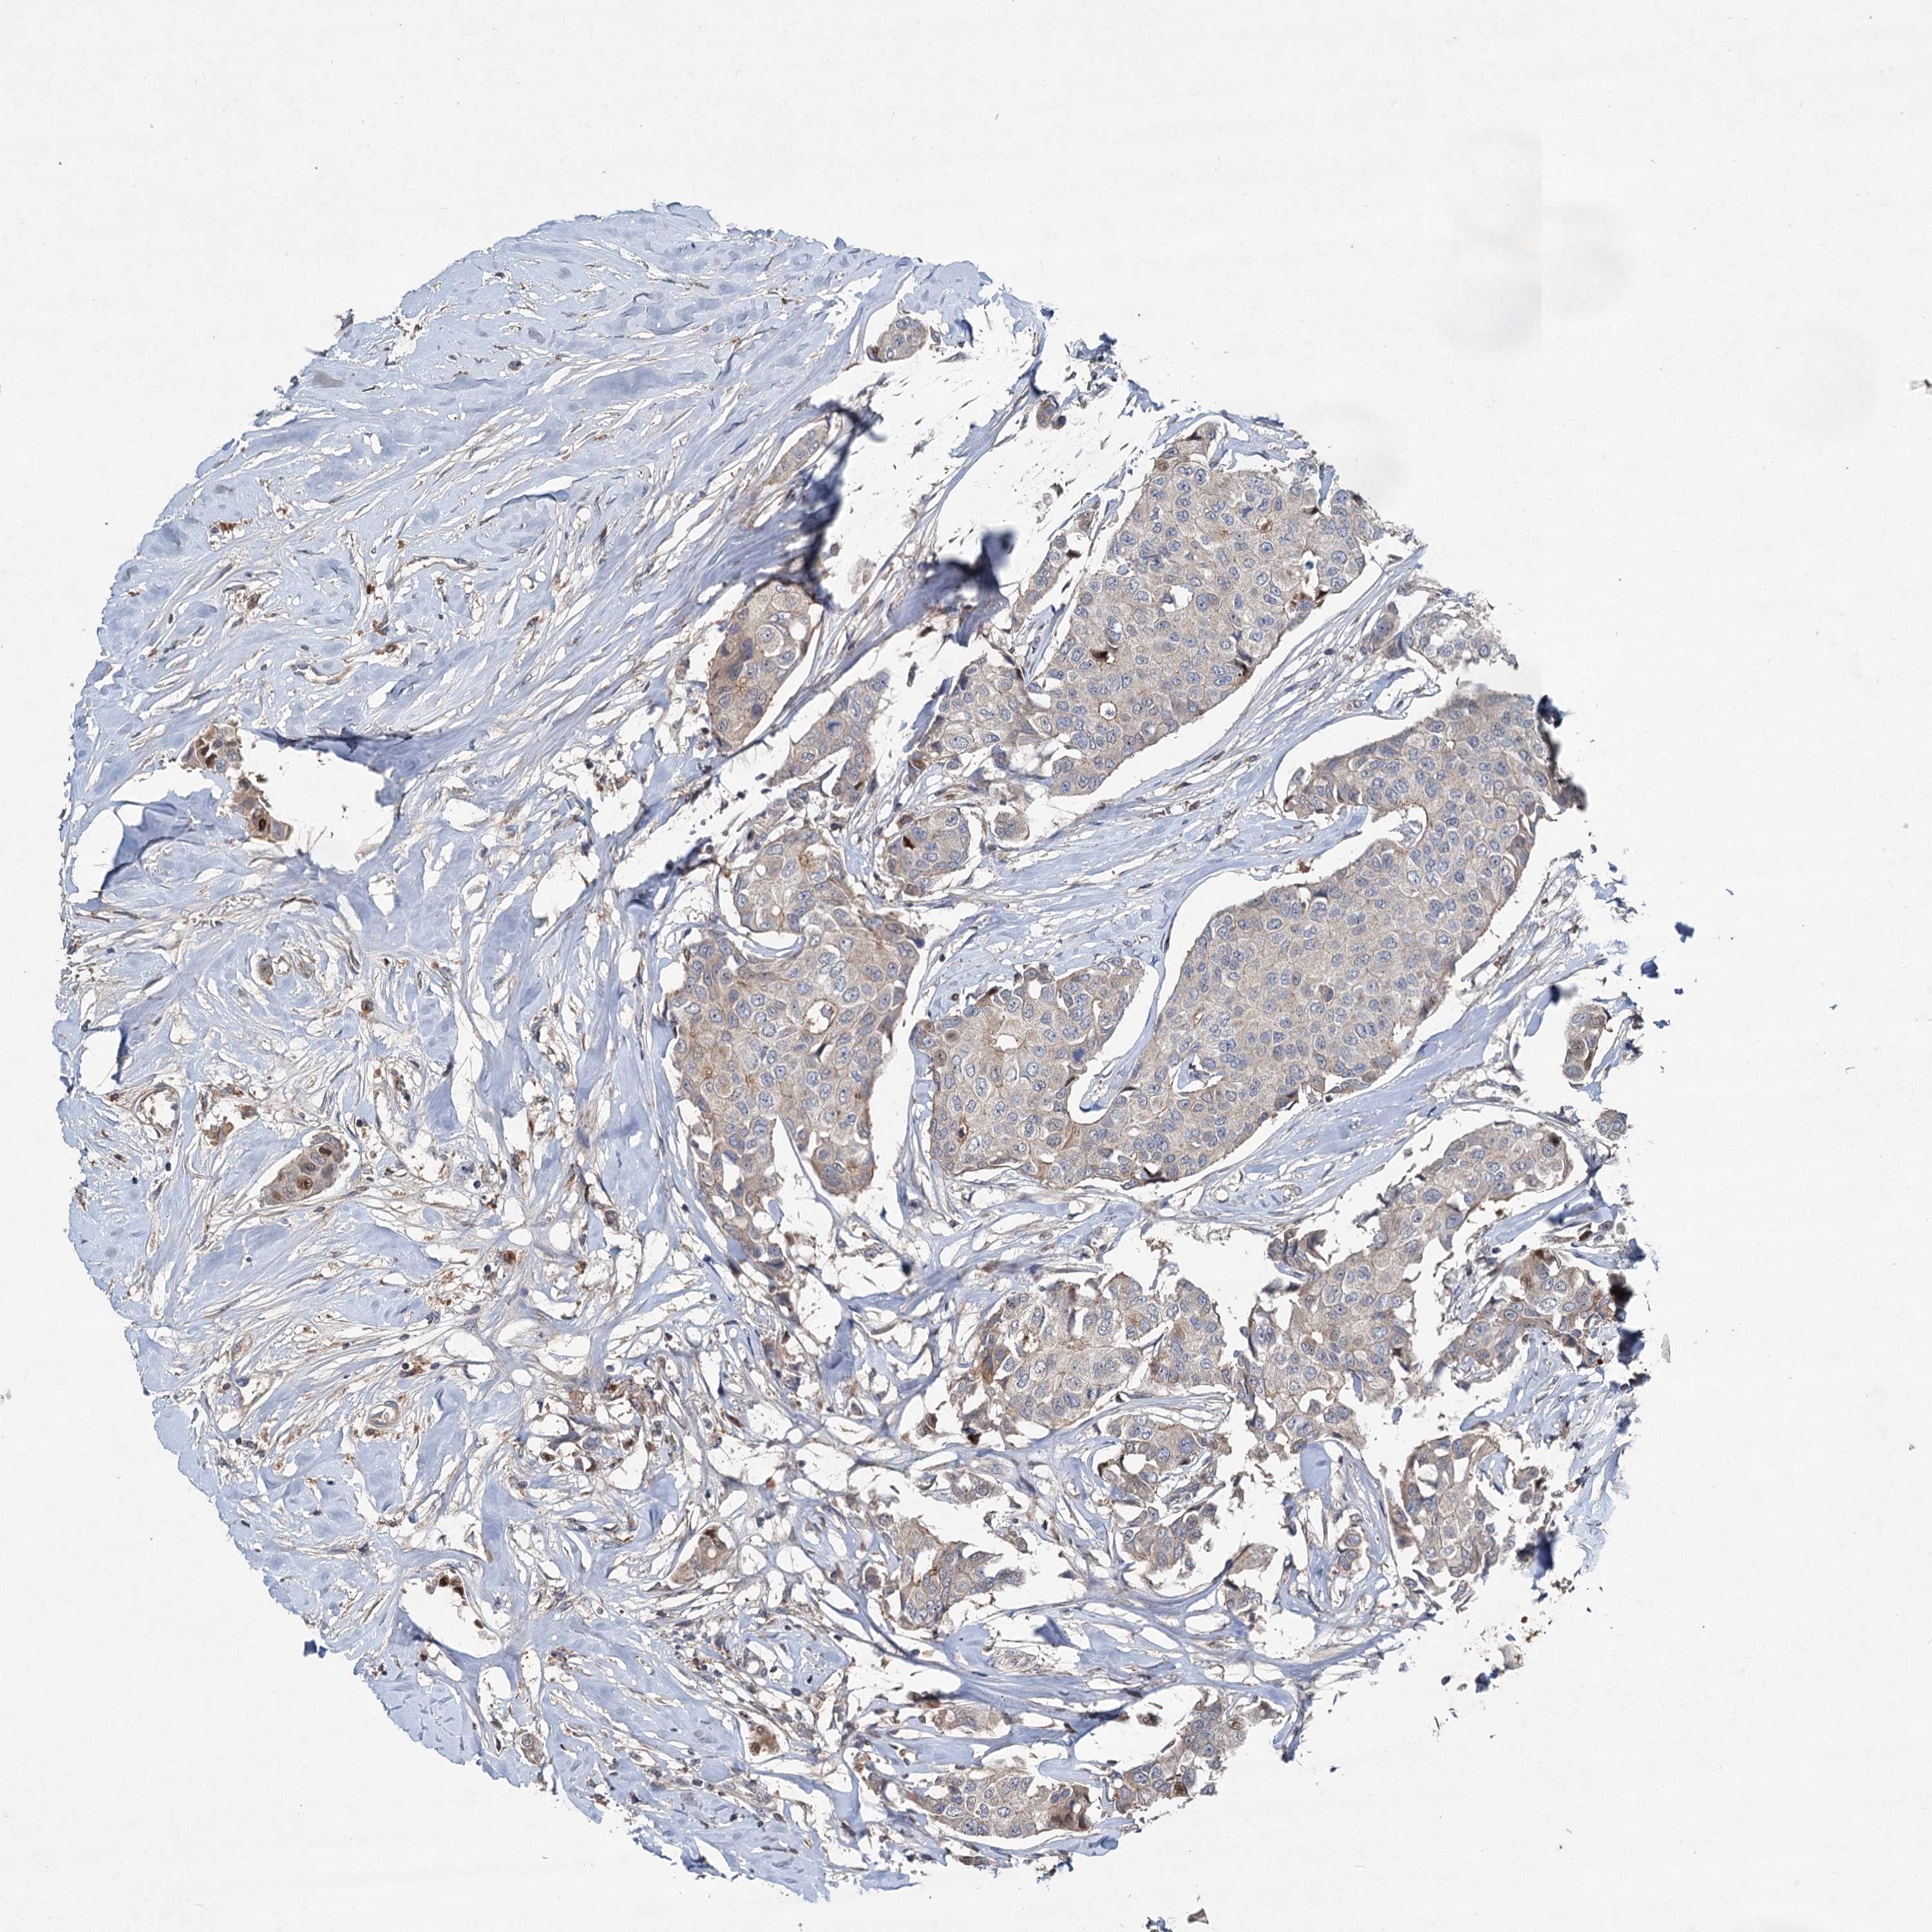

CANCER BREAST CANCER Show tissue menu

BRCA TCGA BRCA VALIDATION PROTEIN EXPRESSION